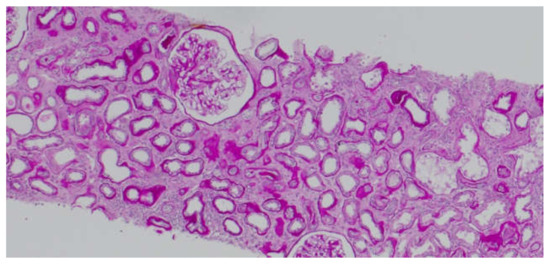

It is known that CD147 abundant in the renal tubules is a very strong activator of MMP-2—the basement membrane-degrading metalloproteinase required for EMT to take place [6]. An in vitro experiment showed that in renal tubular epithelial cells CD147, together with MMP, induces the production of hyaluronic acid, which participates in the differentiation of the tubular epithelial cells into myofibroblasts in response to TGF-β (transforming growth factor β). Hyaluronan promotes the emergence of proteins typical of fibroblasts on the surface of the transforming cells [18]. Similar to AKI, CD147’s role in stimulating inflammatory infiltration by macrophages and monocytes in chronic kidney injury has been proven [19]. CD147 is thought to exacerbate fibrosis following three mechanisms: hyaluronan induction, MMP (particularly MMP-2) induction, and inflammatory infiltration. Our study showed that the concentration of CD147/EMMPRIN correlated negatively with eGFR at the time of sampling—69 months post-Tx on average. The level of serum CD147/EMMPRIN at the end of the follow-up period correlated negatively with eGFR at 1- and 2-years post-Tx, as well. These results prove that its high activity is most apparently linked to worse renal graft function since the very beginning—the early post-transplantation period and at 1- and 2-years post-Tx. Kemmner et al. [6] came to similar conclusions after they analyzed the presence of CD147 in biopsy specimens collected from renal graft recipients (50 months post-Tx on average) in the context of renal graft function and chronic histopathological lesions in the form of IF/TA. They found that abundant CD147 in the biopsy specimen was associated with more pronounced FT/TA lesions, poorer renal graft function evaluated using eGFR values, and an unfavorable change of renal graft function over time [6]. Another researcher, Yoshiko Mori et al., monitored the correlation of urine and plasma CD147 concentrations with renal graft function in patients with different kidney diseases [20]. There is very little information available on EMMPRIN expression in the renal tissue, especially in renal grafts. Most research into this compound is related to cancer and cancer invasion [21]. In many cancers, the effect of EMMPRIN on EMT processes linked to cancer invasion has been proven [21]. EMMPRIN plays a proven role in lung fibrosis secondary to inflammatory diseases [22]. Similar to Kemmner’s results, in our study EMMPRIN correlated positively with IF/TA histopathological lesions. CI demonstrated four degrees of lesion severity (0: ≤5%, 1: 6–25%, 2: 26–50%, 3: >50%), similarly to CT (0: no atrophy, 1: ≤25%, 2: 26–50%, 3: >50%). The more severe interstitial fibrosis and tubular atrophy, the higher the CD147 concentration. Histopathological images of kidney biopsy specimens of two patients with advanced chronic changes in terms of IF/TA have been presented below. In both biopsy specimens, changes have been graded as ci3, ct3, and EMMPRIN concentrations were 12,826 pg/mL and 29,709.47 pg/mL, respectively (Figure 6A,B). Other histopathological images present kidney grafts with no chronic changes. Ci and Ct grades were 0 with less than 5% of the kidney parenchyma being covered with fibrotic changes, and less than 5% of the tubules being atrophic. EMMPRIN concentrations were 3206.734 pg/mL and 897.41 pg/mL, respectively (Figure 7A,B). Another image presents advanced fibrosis (Ci3) with >50% of the kidney parenchyma covered, with <25% of the tubules being atrophic (Ct1). EMMPRIN concentration was 7304 pg/mL in this case (Figure 8).

Figure 6.

Histopathological images showing chronic changes graded as ci3, ct3 (A,B).

Figure 7.

Histopathological images showing chronic changes graded as ci0, ct0 (A,B).

Figure 8.

Histopathological image showing chronic changes graded as ci3, ct1.